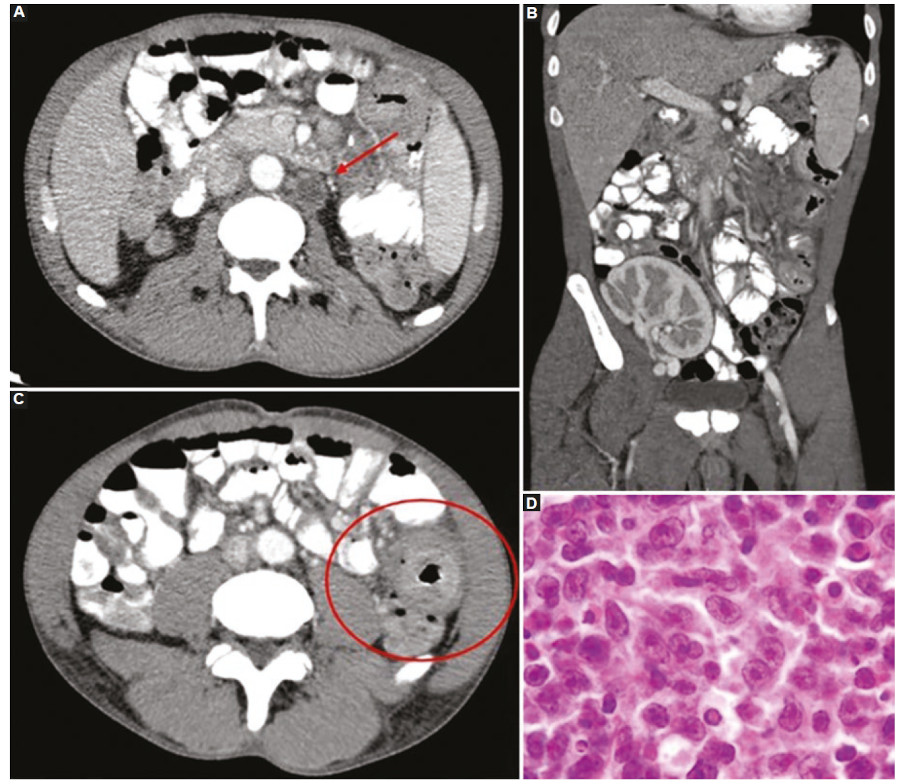

En cuanto a los patrones por imágenes en el SLPT del tracto gastrointestinal se describen el engrosamiento parietal circunferencial, siendo infrecuente que condicione una obstrucción al igual que los demás procesos linfoproliferativos; la dilatación intestinal aneurismática; ulceraciones; invaginaciones de segmentos cortos e imágenes polipoides conformando masas excéntricas11,28,36 (Figs. 5 y 6).

En cuanto a los patrones de afectación de los órganos se mencionan cuatro formas principales, sea como una masa obstructiva a nivel del hilio del órgano, con sus complicaciones a nivel vascular; como una lesión focal única parenquimatosa, lesiones múltiples parenquimatosas o un patrón infiltrativo difuso del órgano cuestión6,11.

Con respecto al hígado, en una serie publicada sobre SLPT por Pickhardt et al.28, combinando pacientes pediátricos y adultos trasplantados, se reportó una afectación hepática del 53% de los casos. La enfermedad en el hígado se presenta principalmente como lesiones focales únicas o múltiples que rondan entre 1-4 cm, hipoecogénicas en el examen ecográfico, sin vascularización en el examen con Doppler color, e hipovasculares y sin calcificaciones en la TC. De modo menos frecuente, se observa un compromiso infiltrativo periportal, que puede obliterar tanto el flujo vascular como el drenaje biliar con dilatación de la vía biliar y las consiguientes complicaciones38,39.